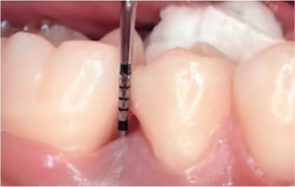

Emdogain Surgical Procedure

STEP 01

Gingival incision

-

STEP 02

Scaling and Root Planing (SRP)